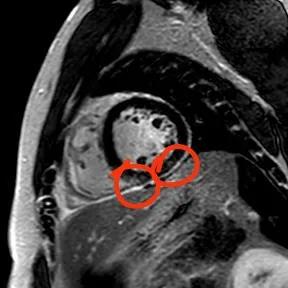

“快!做磁共振觀察心肌有無受損及程度?!庇跋裨\療中心陳寶瑩副主任為小燁進行心臟磁共振平掃及增強掃描。結(jié)果提示:患者有急性心肌損傷,考慮心肌梗死。結(jié)果驗證了小燁的心肌大片區(qū)失活。

方向比努力更重要,對于醫(yī)生而言更是如此,準確把握病因方向,才能有效治療。心臟磁共振,成為非侵入性診斷心肌疾病的金標準,能準確地鑒別心肌炎、應(yīng)激性心肌病、心肌病淀粉樣變性、擴張性心肌病及心肌梗死等,并能對心肌梗死后心肌纖維化進行定量評估。